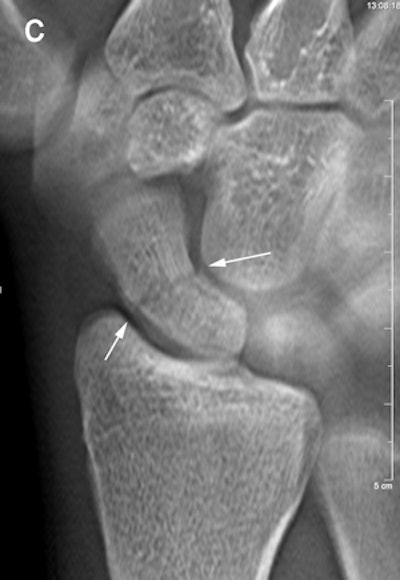

Same patient above. With tomosynthesis (c), a nondisplaced scaphoid wrist fracture was observed in the dorsal cortex (arrows)."Even though we did not reach significance at the two-week follow-up, we still like the increased confidence we get from the addition of tomosynthesis to conventional radiography, and the extra fractures we keep finding," Geijer said.

The trends identified in the pilot study were strong enough to conclude that tomosynthesis can detect occult fractures not visible on radiography.

"The study is noteworthy in that it has shown that radiographically occult fractures can be detected by tomosynthesis, and thus potentially reduce the number of complications after a scaphoid fracture," he wrote to AuntMinnie.com.

The experience also taught the participating radiologists that detecting fractures with tomosynthesis is somewhat different than with conventional radiography and CT. Fracture detection is mainly based on edge disruption with tomosynthesis because the structure of the medullary bone is blurred and not as distinct as in CT, Geijer noted.